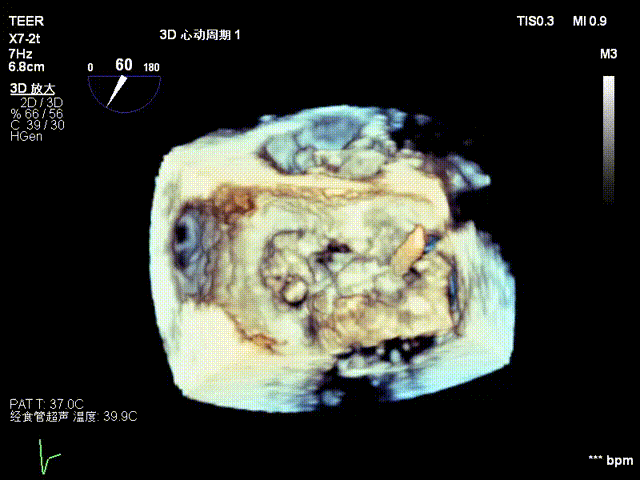

Case 2

患者为56岁男性,因5天前反复出现活动后胸口隐痛感,持续数分钟到数小时不等,超声心动图提示:1.二尖瓣后瓣脱垂并重度关闭不全;2.左心大;3.三尖瓣反流;4.左心收缩功能正常。

经食道超声检查提示:二尖瓣瓣叶增厚冗长2区后瓣脱垂呈连枷样改变,考虑Barlow’s综合征。评估解剖结构:前叶长度:3.3cm,后叶长度:2.8cm,脱垂宽度:26mm,脱垂高度:19mm,瓣口面积:7.5cm²。

术前影像

3D